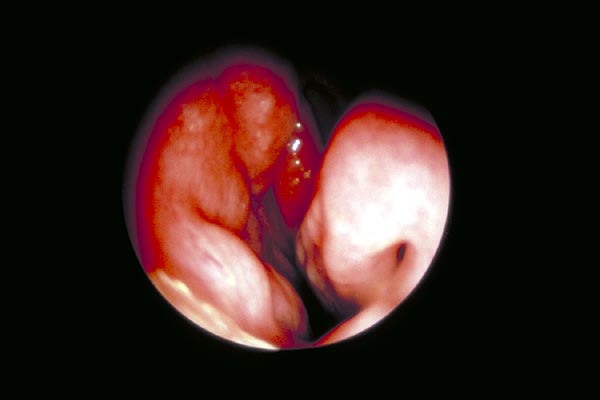

Mit der vorderen Rhinoskopie sehen wir Verdickungen und Verbiegungen des Septums, Synechien, d.h. Verwachsungen zwischen Septum und Muscheln, den Schwellungszustand der Muscheln, die Farbe und Feuchtigkeit der Schleimhaut oder eine Schleim- oder Eiterstrasse aus den Nebenhöhlen.

- Septumverdickung